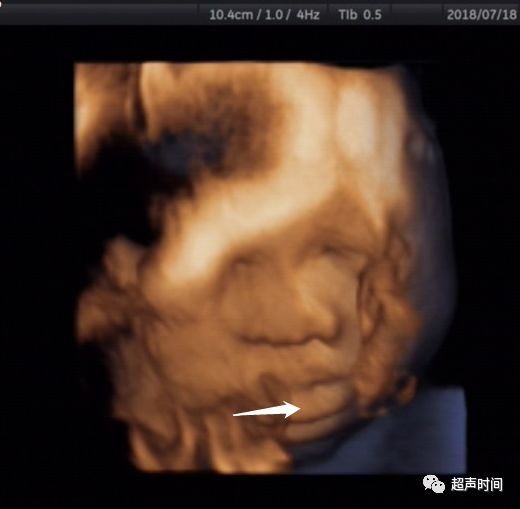

图 3 孕 36 周胎儿面部三维超声示胎儿舌体(箭头示)充满口腔并部分伸出口外

图 4 孕 36 周胎儿面部三维超声示胎儿舌部(箭头示)部分伸出口外